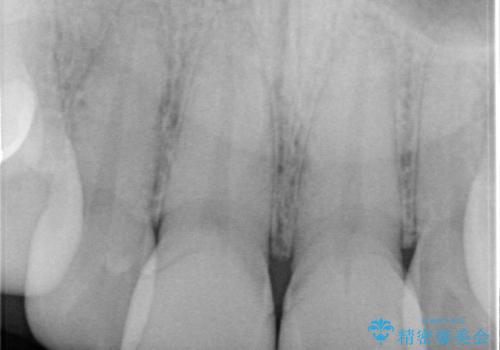

根尖性歯周炎に罹患し根の先に膿が溜まっているのが原因でした。

精密根管治療では、菌を入れない環境を作り見逃しが無いようにマイクロスコープを使って治療する事が大切です。

まだ誰も触っていない根管ならばほとんどのケースで治せる事が出来ます。